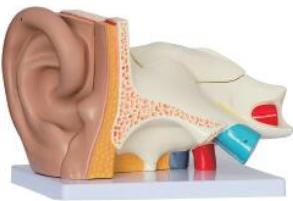

耳(外、中、内)解剖

耳(外、中、内)解剖